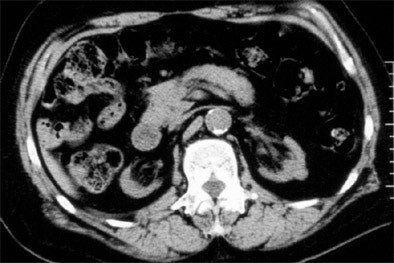

| One of the few patients who clearly met the SICK (small, indented, and calcified kidneys) criteria was a 72-year-old male with progressive analgesic nephropathy. Image above shows increased parenchymal thickness, coarse papillary calcifications bilaterally, and numerous indentations. |

Overall, CT scan detected just 5/19 heavy analgesic users, for a sensitivity of just 26%, though there were no false-positives, Brubaker said. Excluding phenacetin users left just 2/16 heavy analgesic users detected using noncontrast CT, a sensitivity of just 13%. Overall, 191/221 patients had negative CT exams; specificity was 95%.

"We do believe that there is an association between SICK and heavy analgesic use," Brubaker concluded. "But it's largely dependent on phenacetin, so it's not of much interest at the moment. Our main conclusion is that the noncontrast CT scan is not a sensitive diagnostic tool for analgesic nephropathy in the U.S., because the majority of heavy analgesic users do not meet the CT criteria for SICK. And last, we think that SICK is rare in the U.S., occurring in only about 1% of our ESRD population."